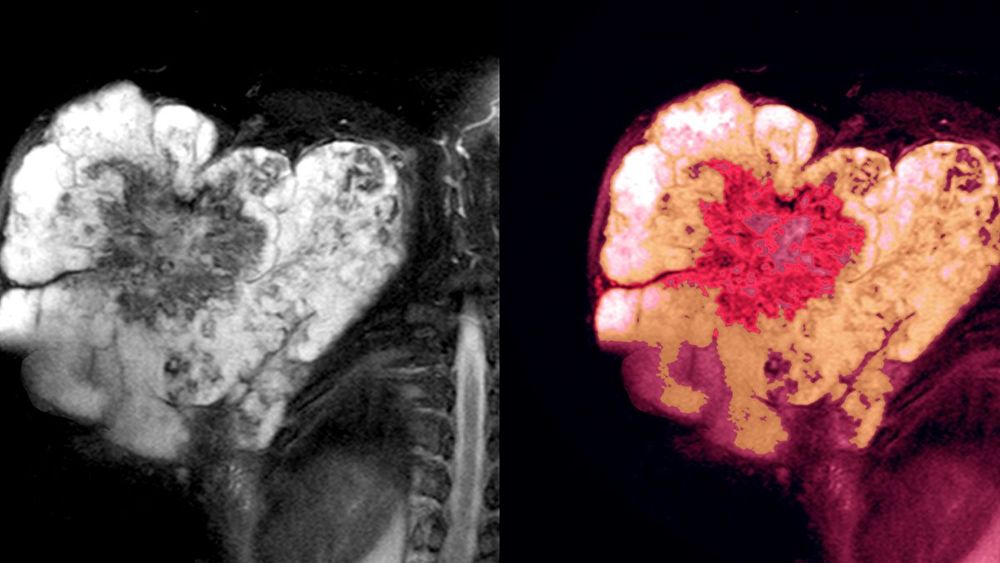

Patienten mit Hochrisikoweichteilsarkomen (FNCLCC-Grad 2–3, > 5 cm und tief gelegen) haben ein hohes Risiko sowohl für das Auftreten eines Lokalrezidivs als auch von Fernmetastasen trotz bestmöglicher Tumorresektion. Es sollte daher ein multimodales Vorgehen für die Therapie dieser prognostisch ungünstigen Tumoren gewählt werden. Neben Chirurgie, Strahlentherapie und Chemotherapie bildet die Hyperthermie die 4. Säule im Kontext multimodaler Behandlungskonzepte. Hyperthermie meint dabei die über Mikrowelleneinstrahlung möglichst selektive Erwärmung der tumortragenden Region auf Temperaturen von 40–43 °C für eine Zeitdauer von 60 min in Ergänzung zu einer simultanen Chemotherapie oder Strahlentherapie. In einer randomisierten Phase-III-Studie konnte durch die Hinzunahme der Hyperthermie zu einer neoadjuvanten Chemotherapie eine deutliche Verbesserung des Tumoransprechens verbunden mit einem sehr niedrigen Risiko der Frühprogression gegenüber alleiniger Chemotherapie gezeigt werden.

Die Hinzunahme der Hyperthermie zu einer multimodalen Therapie bei Patienten mit Hochrisikoweichteilsarkomen, bestehend aus Chirurgie, Strahlentherapie und Chemotherapie, entweder neoadjuvant oder auch adjuvant nach einer unvollständigen bzw. marginalen Tumorresektion, führten zu einer signifikanten Verbesserung des lokalrezidiv- und krankheitsfreien Überlebens. Basierend auf diesen Ergebnissen und in Verbindung mit der nur moderaten zusätzlichen Belastung des Patienten durch eine Hyperthermiebehandlung sollte der Einsatz dieses Verfahrens in Kombination mit einer Chemotherapie im Rahmen multimodaler Therapieansätze als Standardtherapieoption erwogen werden.